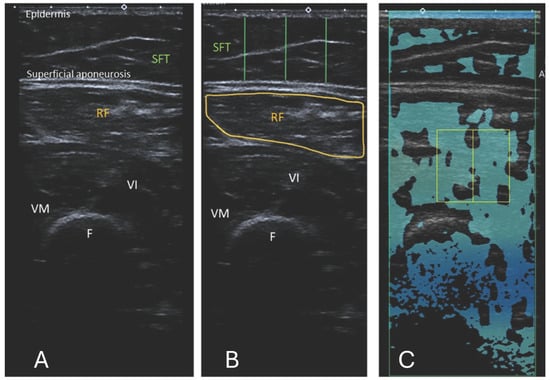

10 US images were obtained for RF and 5 for BB (15 images per participant total), as shown in Figure 1 and Figure 2. The images were anonymised and saved as DICOM files for EI measurements.

Figure 1. (A) Ultrasound B-mode image of the RF, musculus vastus intermedius, and medius. The distance between the epidermis and superficial aponeurosis is defined as subcutaneous fat tissue (SFT). (B) Segmented image of the RF, including the muscle cross-sectional area and the lines marking the thickness of the SFT from the lateral, central, and medial aspects of the RF. The measurement of the SFT was taken at 25%, 50%, and 75% of the total muscle visible on ultrasound, respectively. (C) Attenuation imaging of the RF. The green box indicates the area of interest (AOI), and the yellow box indicates the region of interest (ROI) placed within the quadriceps femoris muscles. RF = rectus femoris, VI = vastus intermedius, VM = vastus medialis, SFT = subcutaneous fat tissue, F = femur.

2.2.1. Echo Intensity

The images were processed using a computer-assisted greyscale analysis using ImageJ software (version 1.54h) [34]. Echo intensity is defined as the mean pixel intensity within the region of interest (ROI) and was calculated using the histogram function. The mean voxel intensity is expressed as a value ranging between black (0 arbitrary units) and white (255 arbitrary units). The RF and BB muscle cross-sections were circled manually to include as much of the muscle as possible, excluding any bone or surrounding myofascial tissue, as shown in Figure 1B and Figure 2B. A total of 5 consecutive images per level were taken, and the muscle was circled manually. The average of the 5 measurements was used in the analysis. When it was insufficient to display the entire muscle, only a part of the muscle was used for EI analysis. EI is taken only from transverse images for a fair and accurate comparison with ATI. The thickness of the subcutaneous fat tissue (SFT) was defined as the length from the epidermis to the superficial aponeurosis. For each transverse image, the SFT was drawn at 25%, 50%, and 75% of the total length of the BB or RF muscle visible on the ultrasound image, as shown in Figure 1B and Figure 2B. The average of these 3 lines was taken to have the distance for SFT. The average of the 5 measurements for SFT was used in the final analysis.

2.2.3. Attenuation Imaging

The commercially available Canon linear array i11LX3 (Canon, Otawara-shi, Japan) with a centre frequency of 7 MHz was used to complete ATI of the RF and BB muscles. Attenuation imaging general (ATI-Gen) was the pre-set of the Aplio i800. The machine settings, such as a gain of 76 dB and dynamic range of 60, were kept consistent between participants. The depth of the image field was 10 cm when the area of interest (AOI) box was at maximum and as near to the middle of the frame as feasible, as shown in Figure 1C for RF and Figure 2C for BB. The ROI box was made to cover as small an area as possible (2 × 2 cm) and moved on the image so that R2 was greater than 0.85. Previous studies used an R2 value of 0.7 [24]; hence, 0.85 was deemed acceptable here. The box was positioned on the thigh to contain only the RF, where possible. This was not always possible due to the limitations in the smallest area of ROI available. In this case, the box was positioned on the RF, vastus intermedius, and medius muscles, including myofascial tissue. As the transverse cross-section of BB muscle is larger, the box can be positioned here so that no bone or muscle fascia lies on it as far as possible. Examples of the ATI measurement are shown in Figure 1 and Figure 2.